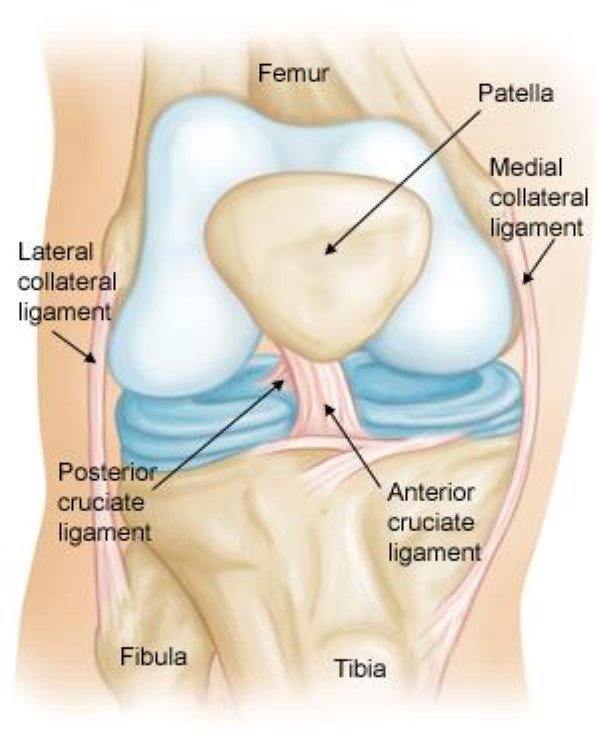

The Anterior Cruciate Ligament (ACL) is one of the most important ligaments of the knee joint. It connects the femur (thigh bone) to the tibia (shin bone) and provides stability during activities like running, pivoting, and sudden direction changes.

• Clinical examination (Lachman test, Pivot shift test)

• MRI scan to confirm ligament tear